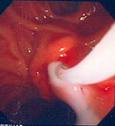

Drenaje biliar precoz

Aunque el tratamiento clásico ha sido el drenaje quirúrgico (colecistectomia, coledocotomia, extracción de cálculos, lavados, y drenaje biliar trancístico o en T de Kher, acompañado o no de un drenaje interno de la vía biliar ), su elevada mortalidad en presencia de sepsis y los buenos resultados del drenaje no quirúrgico han declinado la balanza a favor de estos últimos. Tanto el drenaje percutáneo (CTPH) como el endoscópico (CPRE) son alternativas eficaces al quirúrgico, pero se prefiere este ultimo por sus menores complicaciones y porque permite habitualmente el tratamiento definitivo de la coledocolitiasis.

El drenaje endoscópico precoz presenta una tasa de complicaciones y mortalidad significativamente inferiores al quirúrgico, por lo que actualmente se considera de elección en el tratamiento de la colangitis aguda grave ( colecistectomia diferida ( electiva) por vía laparoscópica). Si el estado de la coagulación lo permite se realizara la técnica habitual con esfinterotomía y extracción de los cálculos. Pero incluso con alteraciones de la coagulación se puede colocar un catéter nasobiliar o una endoprótesis sin hacer esfinterotomia, demorando un tratamiento mas definitivo para cuando mejoren las condiciones del paciente.